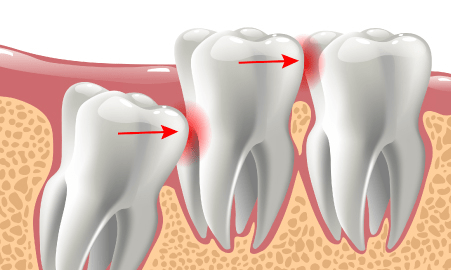

- 歯が押されて歯並びが変わってしまう

親知らず(第3大臼歯)の一つ手前の歯(第2大臼歯)は、咬み合わせに重要な歯です。

親知らずが周囲に悪影響をもたらしている場合は、早めの抜歯をお勧めしています。

- 第2大臼歯が親知らずのために、むし歯や歯周病が進行している場合や、将来的にそのリスクが高い場合

- 第2大臼歯の歯の根に、親知らずが当たっている

親知らずは、まれに隣の歯を圧迫するような生え方で成長することがあります。